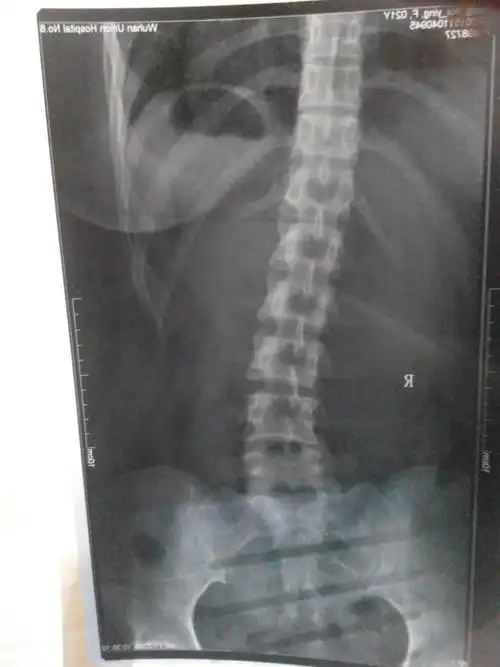

62脊柱侧弯孩子两年的治疗经历

从左到右:2016年,侧弯度数35度.2017年胸弯减少到18度.

病例15岁男孩脊柱侧弯35戴gbw支具下拍片减至10